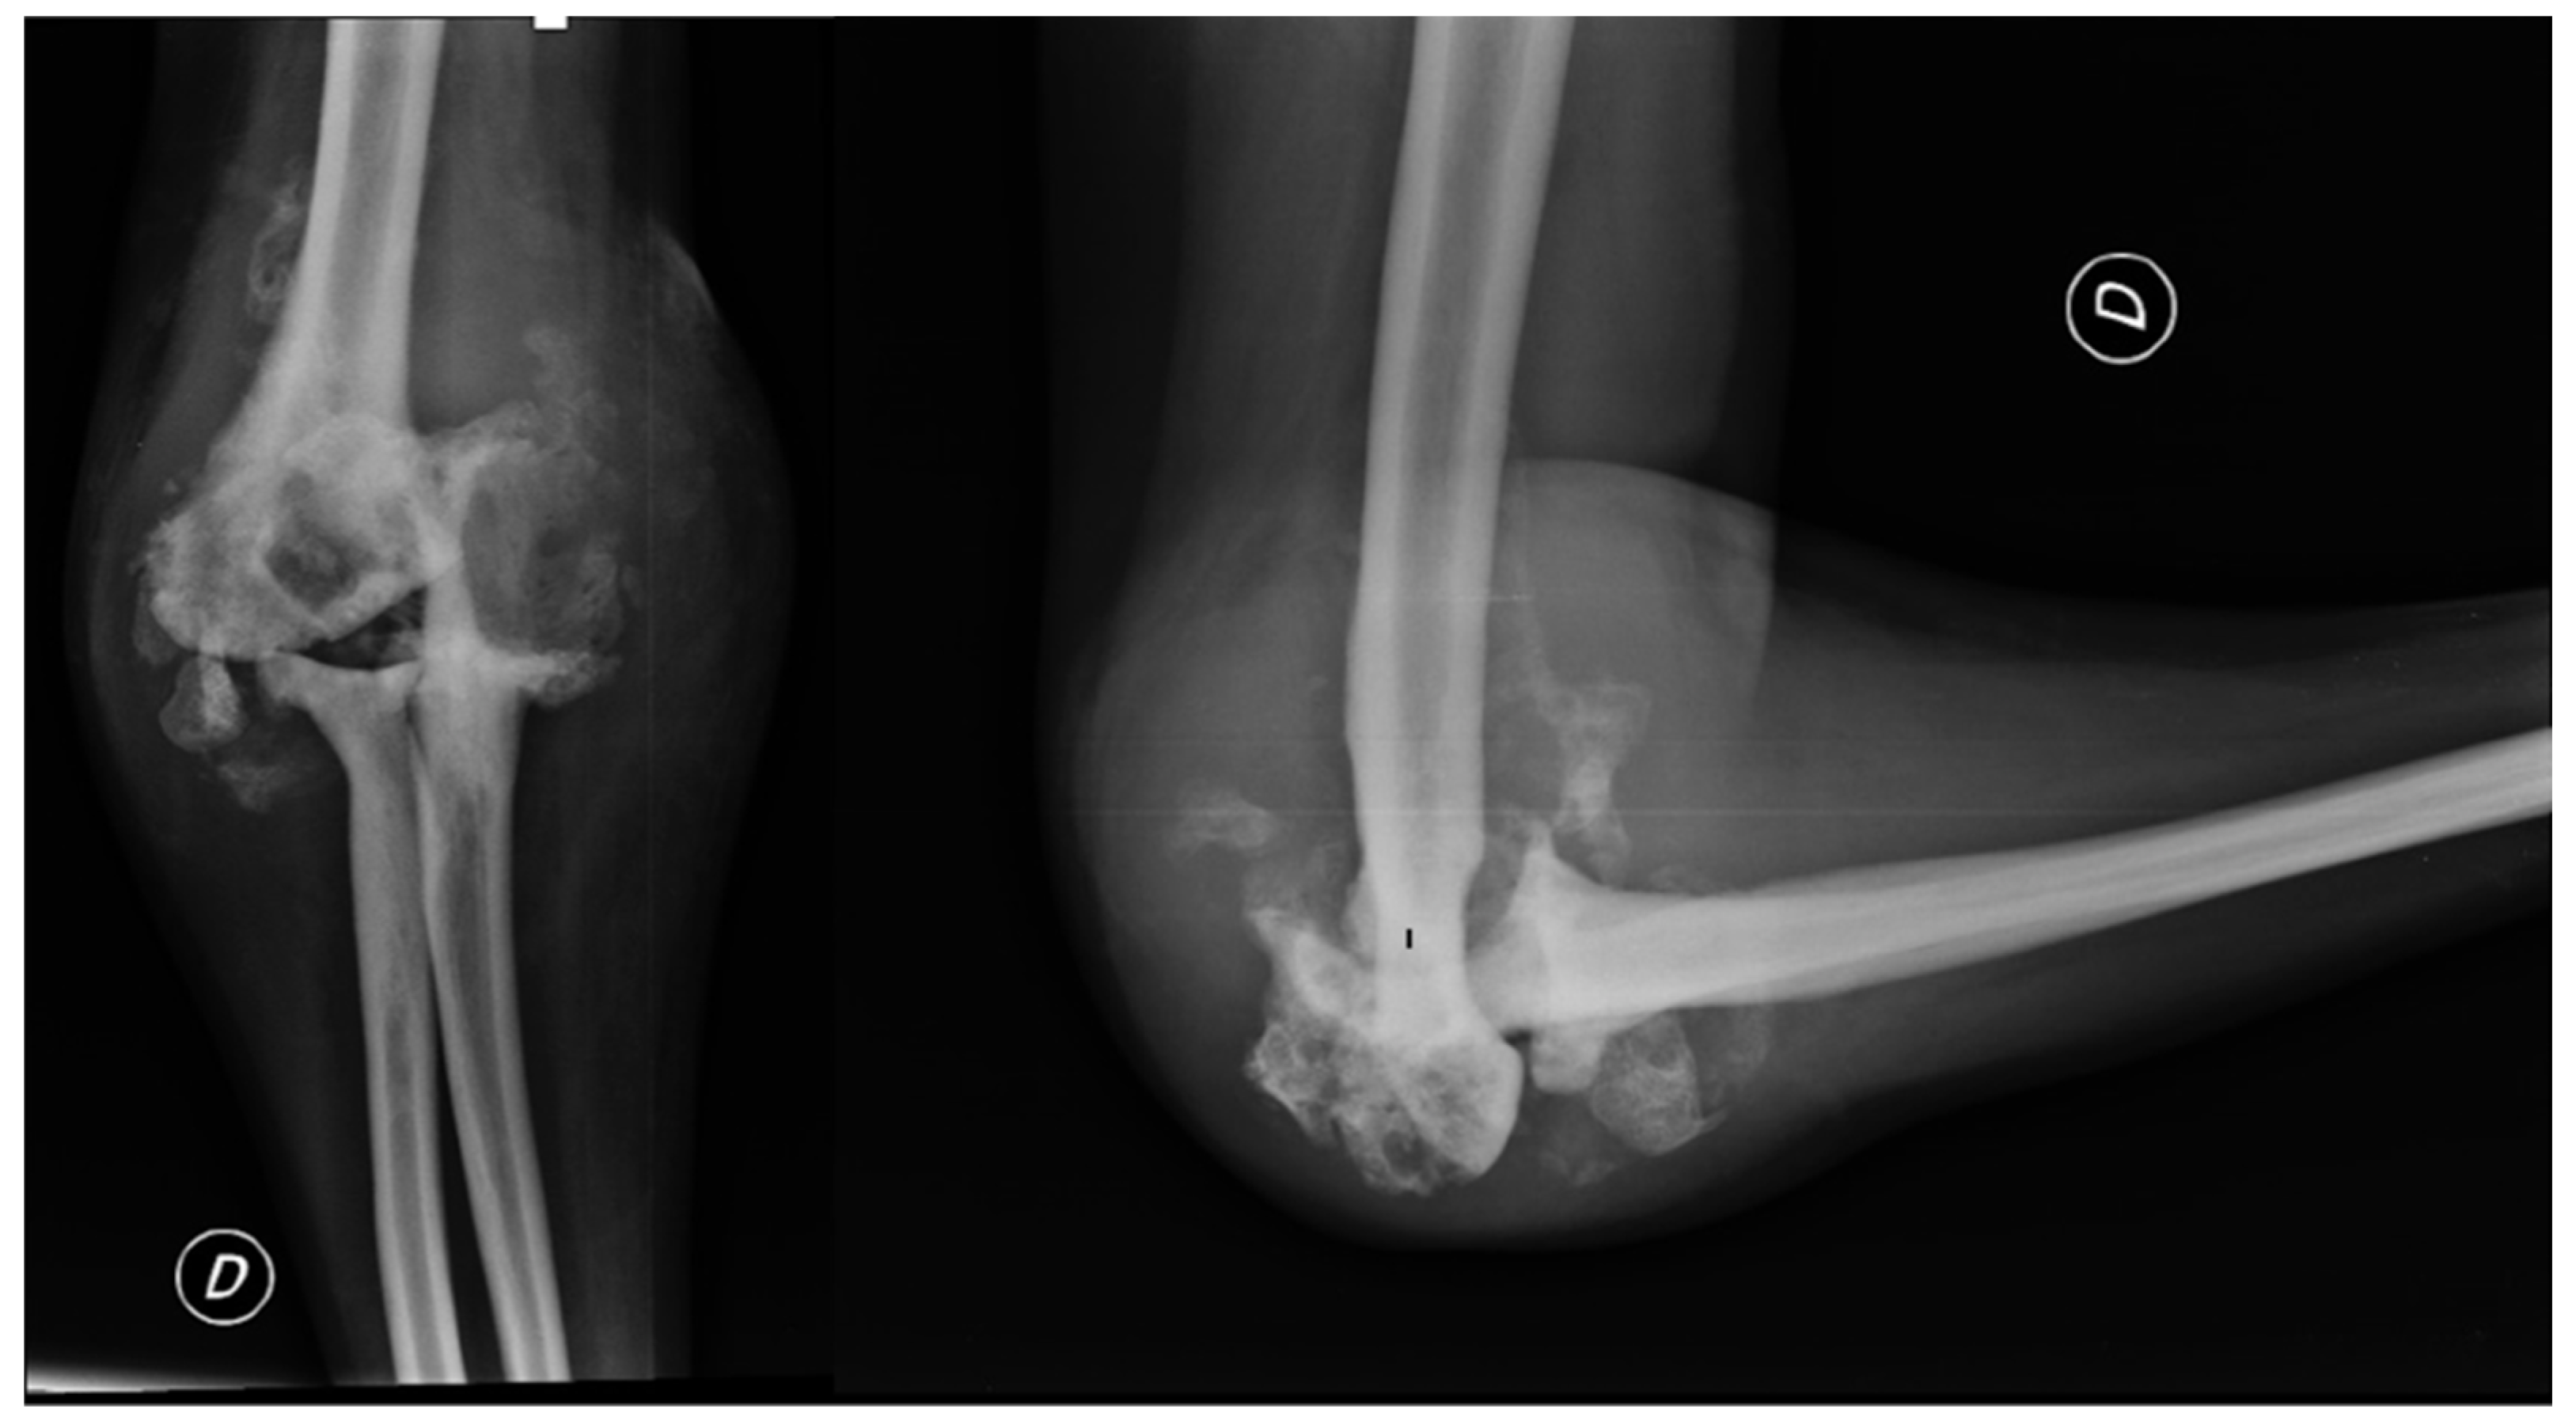

In April 2012, the patient underwent open debridement with synovectomy and removal of bone fragments in arthroscopy due to the advanced stage of hemophilic elbow arthropathy. During the procedure, bone resorption phenomena with free fragments were observed in the joint, mainly at the radial head, and the capsule was thickened with evidence of synovitis. The dislocation was structured and non-reducible. Samples of bone and synovium were taken and cultured for pathogen microorganisms, which turned out positive for different types of coagulase-negative Staphylococcus. Postoperative X-ray showed the removal of some fragments at the joint level, but the elbow joint dislocation persisted (Figure 3). Synovium fragments showed fibrosis, calcifications, scattered foci of chronic inflammation, synovial hyperplasia, and abundant superficial fibrin stores. Bone samples showed trabecular remodeling and peritrabecular fibrosis with spared perivascular reactive lymphoid aggregates.

Figure 3. Post synovectomy and debridement surgery anteroposterior and lateral views of the right elbow.